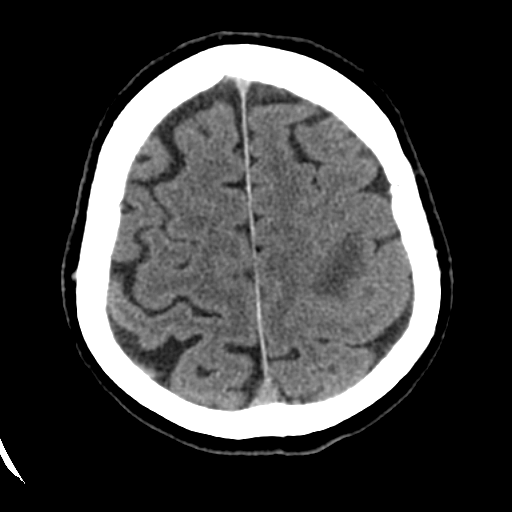

Иллюстрации и пояснения: гиподенсивный очаг на КТ головного мозга